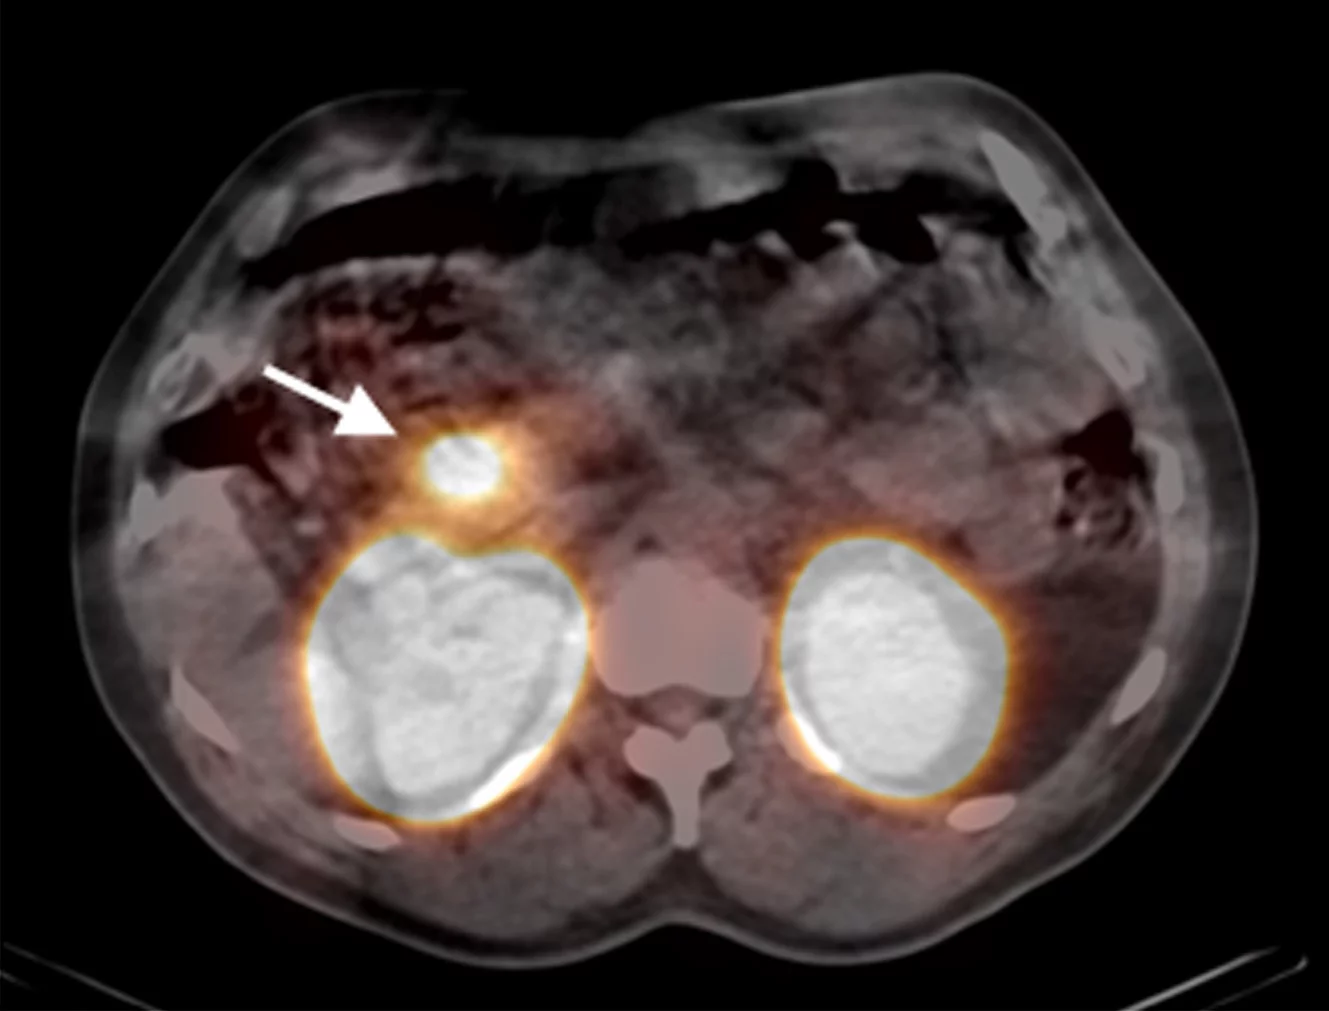

The arrow points to the accumulation of the low-level radioactive substance in the insulinoma. In this case, the insulinoma was localized in the head of the pancreas. As the substance is released through the kidneys, the kidneys are visible as well. (Picture: Nuklearmedizin, Universitätsklinikum Freiburg i. Br.)

In order to localize the insulinomas, the researchers injected an artificial substance combined with low-level radioactive indium into thirty patients with a strong suspicion of insulinomas. The substance accumulates in the tumour and, thanks to its low-level radioactive radiation, renders the mini-tumour visible in a special camera. As a result, ninety-five per cent of the insulinomas could be localised. With CT or MRI, the detection rate would only have been forty-seven per cent. “It is likely that this method will replace the existing invasive methods for locating insulinomas in the future,” says Professor Emanuel Christ from the Inselspital Berne, the endocrinologist (metabolism specialist) responsible for this research project.